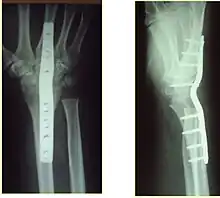

The techniques of surgical management include open reduction internal fixation (ORIF), external fixation, percutaneous pinning, or some combination of the above. The choice of operative treatment is often determined by the type of fracture, which can be categorized broadly into three groups: partial articular fractures, displaced articular fractures, and metaphyseal unstable extra- or minimal articular fractures.[4]

Significant advances have been made in ORIF treatments. Two newer treatment are fragment-specific fixation and fixed-angle volar plating. These attempt fixation rigid enough to allow almost immediate mobility, in an effort to minimize stiffness and improve ultimate function; no improved final outcome from early mobilization (prior to 6 weeks after surgical fixation) has been shown. Although restoration of radiocarpal alignment is thought to be of obvious importance, the exact amount of angulation, shortening, intra-articular gap/step which impact final function are not exactly known. The alignment of the DRUJ is also important, as this can be a source of a pain and loss of rotation after final healing and maximum recovery.

Surgical options have been shown to be successful in patients with unstable extra-articular or minimal articular distal radius fractures. These options include percutaneous pinning, external fixation, and ORIF using plating. Patients with low functional demand of their wrists can be treated successfully with nonsurgical management; however, in more active and fit patients with fractures that are reducible by closed means, nonbridging external fixation is preferred, as it has less serious complications when compared to other surgical options.[4] The most common complication associated with nonbridging external fixation is pin tract infection, which can be managed with antibiotics and frequent dressing changes, and rarely results in reoperation.[4] The external fixator is placed for 5 to 6 weeks and can be removed in an outpatient setting.[4]

If the fractures are unlikely to be reduced by closed means, open reduction with internal plate fixation is preferred.[4] Although major complications (i.e. tendon injury, fracture collapse, or malunion) result in higher reoperation rates (36.5%) compared to external fixation (6%), ORIF is preferred, as this provides better stability and restoration of the volar tilt.[4][20] Following the operation, a removable splint is placed for 2 weeks, during which time patients should mobilize the wrist as tolerated.[4]